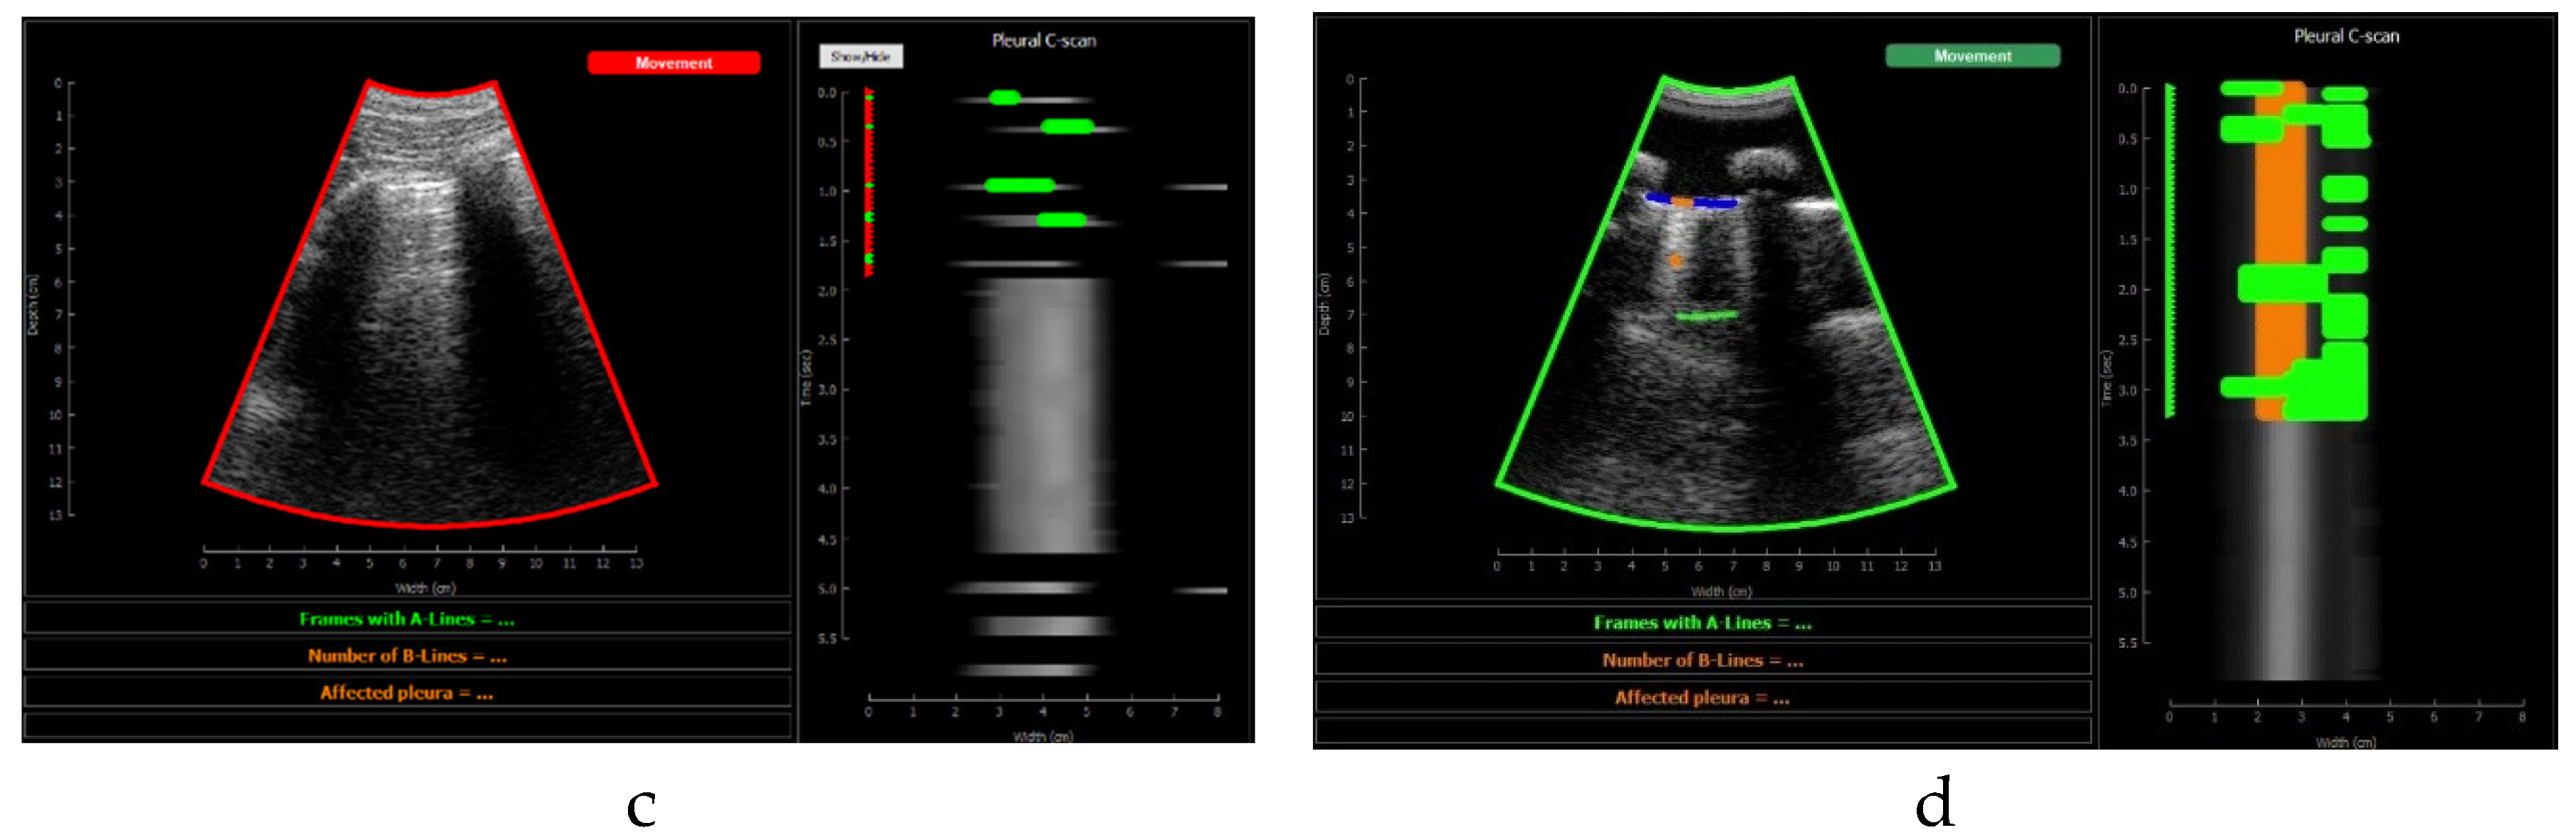

2.9.1. Pre-Processing Block

Pre-processing algorithms are carried out before executing the Deep Learning model. These algorithms serve as a preliminary filtering steps to avoid processing images that do not meet the quality criteria for evaluation. First, probe movement is verified, because acquisitions where the probe is not held still cannot be analyzed. Using optical flow algorithms [23,24], probe movement is estimated between two consecutive images, using reference points located in the upper part of the image (muscle and fat). A movement threshold of 2 mm/s was established. If the image does not meet the criteria, it is not processed, and it will be displayed on the screen with a red label indicating movement (see in Figure 12.d). If, on the contrary, it meets the requirements, a green label will be displayed on the screen (Figure 12.c) and the rest of the processing will be executed.

Figure 10 shows the screen shown to the user. On the left, the acquired sector-scan images are shown in real-time, with several overlays coming from the processing algorithm. When the image is valid for being evaluated, the contour of the image turns green, and so the label “movement” on the upper right corner. If the image fails to pass any of this criterion, the contour line turns red, and so the labels that triggered the event. Therefore, the physician can freely move the probe on the patient chest until theses indications turn green, and then hold probe steady to acquire a video of 3 seconds that will be saved for each of the 12 regions to be examined according to the protocol.

This image also overlays, in real-time, the findings of the neural network. The pleura is marked with blue points, A-Lines with green points, B-Lines with orange points and consolidations with red points. Furthermore, a series of statistics and messages are shown in the lower part of this image: The percentage of frames with A-Lines in the last 6 seconds, the number of isolated B-Lines, calculated as the sub-regions with an average 6dB drop in the angular direction within the region where B-Lines were detected, the percentage of the affected pleura calculated as the number of scan lines affected by B-Lines over the total number of scan lines where the pleura was detected, and a label in red indicating that a consolidation when present.

On the right of the screen an image we refer as pleura C-scan is shown. The C-Scan is a type of image widely used in Non-destructive Testing (NDT) applications where B-scan images are acquired while the probe is moving and a visual representation of the whole component is needed [29]. For each image line within the B-Scan, the maximum amplitude is obtained within a gate at some depth, which ensembles an image that can be interpreted like a top view of the component, with defects information at a certain depth. We adapted this concept using a gate at the depth of the pleura, obtained from the pleura mask given by the model, and substituting the mechanical movement of the probe in an NDT scan, by the time index in the acquired video. Therefore, each horizontal line in the pleura C-Scan correspond to a frame in the video, and it shows the brightness of the pleura line along the horizontal dimension of the image. At each of these lines landmarks with the previously defined colours are also plotted. As the video progresses, the C-Scan image is constructed frame by frame from top to bottom and, at the end, all the relevant information of the video is condensed in only one image. The presence of A-Lines, B-Lines and consolidations and their extension with regard to the pleura width can be appreciated, and also the pleura sliding effect as the indications move laterally during the scan. Furthermore, these images could be saved for each acquired region in the chest, and shown in a single panel that depicts the global condition of the lung in a single view, without the need to review each of the acquired videos for the whole examination, which could help to reduce time during follow up of patients.

Figure 13 shows several examples of the screen of the implemented software in operation explained in Section F.4.

Figure 13. Application visualization sample: a)B-lines (orange) and consolidation (red) detection; b)normal lung with A-lines(green); c) probe movement detected; d) B line (orange) and A-line (green) deteccion on a Lung phantom. On the right of each image the C-scan image is shown.